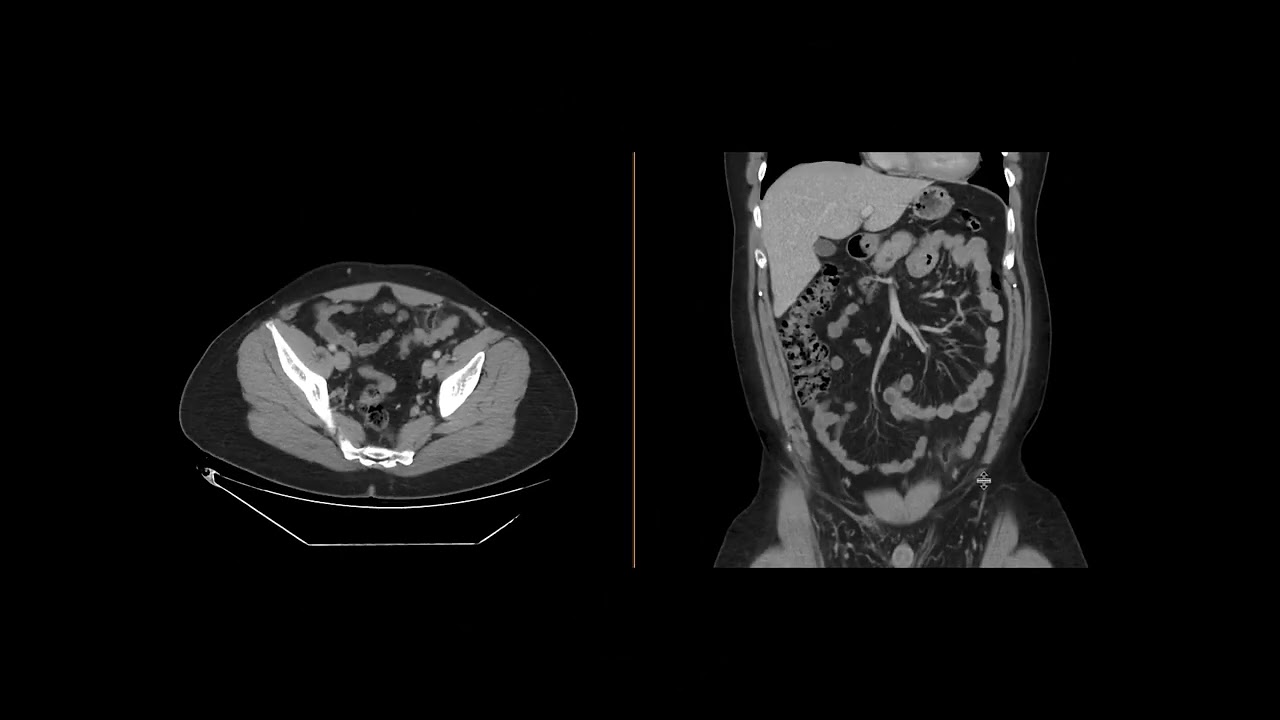

Epiploic appendagitis (Ahuja AT et al; 2017) Book: Essential Radiology

Описание: Axial CECT shows a circumscribed fat density lesion in right upper abdomen. There is central hyperdense dot representing a thrombosed vessel. Features are compatible with epiploic appendagitis.